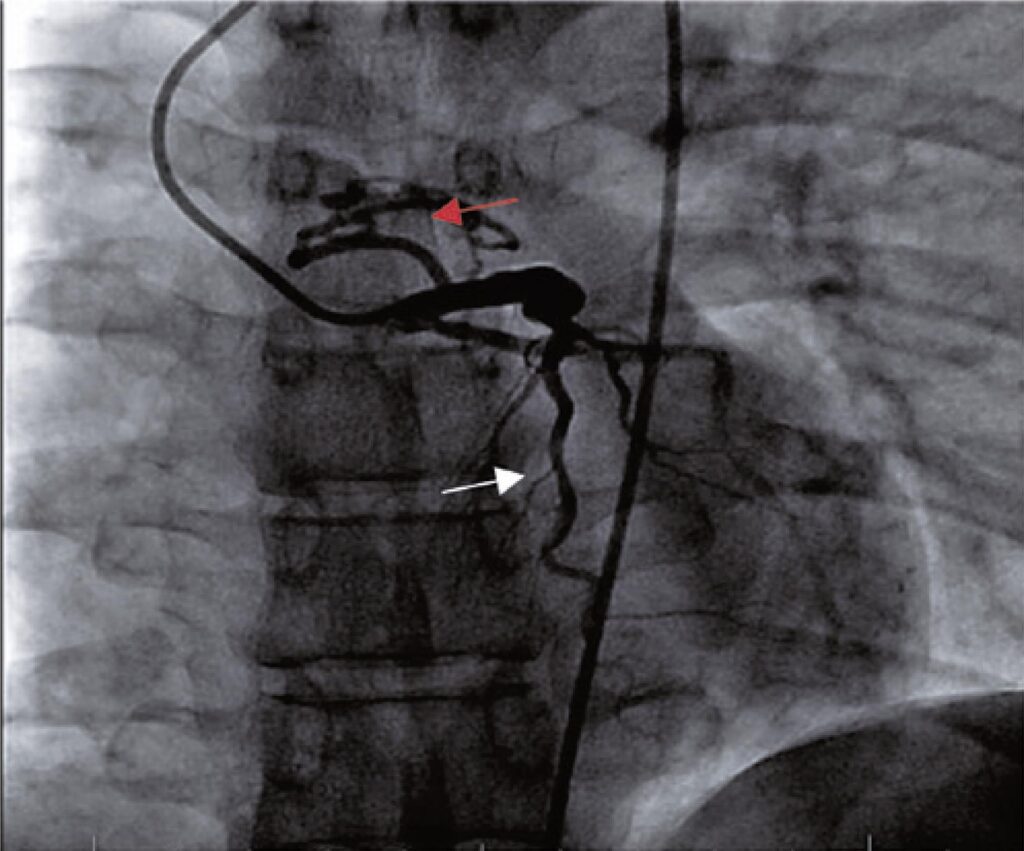

Left anterior descending artery fistula to pulmonary artery

Congenital anomalies and within them anatomical variations of coronary arteries, although uncommon, are being increasingly studied and diagnosed due to the close relationship of symptoms such as angina, dyspnea, syncope or arrhythmias in young people without comorbidities. This study aimed to present the case report of a patient with ischemic symptoms secondary to malformation of a coronary artery. We describe the moment of patient admission, diagnosis by complementary tests and therapeutic resolution of the case. Coronary fistulas, despite having a low incidence among congenital heart diseases, have become increasingly frequent, being better characteristic due to new diagnostic methods.